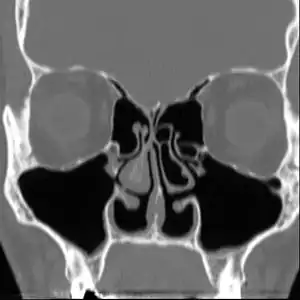

Diagnosis

No consensus criteria exist for the diagnosis of ENS and many ENTs will wait a year before diagnosing in hopes the patient accepts the new airflow; it is typically diagnosed by ruling out other conditions, with ENS remaining the likely diagnosis if the signs and symptoms are present.[4][5][9] A "cotton test" has been proposed, in which moist cotton is held where a turbinate should be or in various locations in the nasal passages, to see if it provides relief and an airflow pattern that allows for natural breathing; while this has not been validated nor is it widely accepted, it may be useful to identify which people may benefit from surgery.[4][5][9]

As of 2015, protocols for using rhinomanometry to diagnose ENS and measure response to surgery were under development,[5][9] as was a standardized clinical instrument (a well defined and validated questionnaire) to obtain more useful reporting of symptoms.[9]